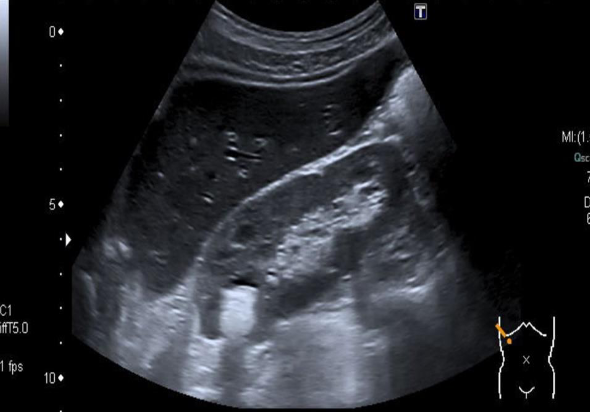

Target sign in intussusception

Ultrasound abdomen (bowel; transverse plane)

Concentric alternating hyperechoic and hypoechoic rings are visible.. Together the alternating

layers produce a target-like appearance (target sign)